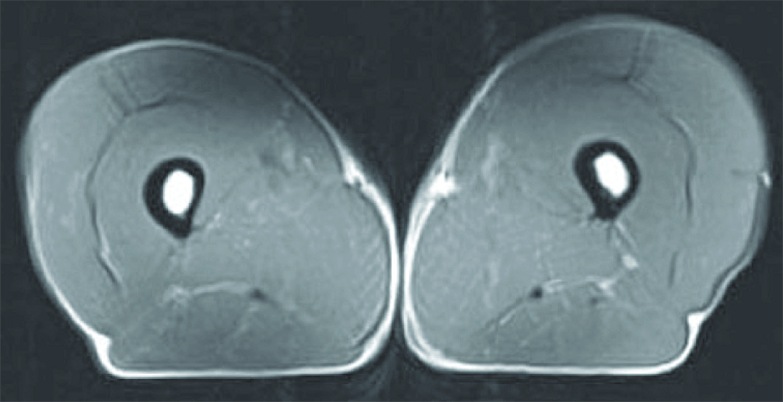

Sarcopenia, defined as age-related, involuntary loss of muscle mass and strength, is inevitable but ONLY if you do not takes steps to counteract it. These incredible MRI images show a cross section of a thigh of a 70 year old man who has done no strength exercise and allowed nature to take its course. The one on the right is a triathlete of the same age. There was a third image that I haven’t featured which compared the 70 year old with a 40 year old triathlete – there was very little difference.

Studies have shown that it is more than possible to build muscle whatever your age, and the good news is, the changes can happen relatively quickly.